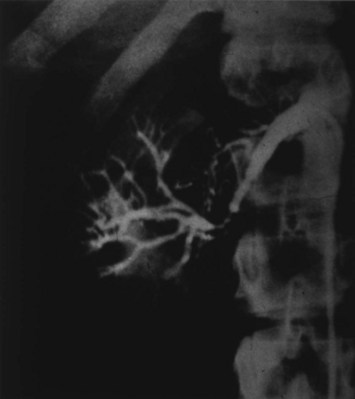

Medial fibroplasia accounts for 75% to 80% of fibrous lesions primarily in women between 25 and 50 years of age. With angiography, arteries demonstrate a “string of beads” in the distal two thirds of the main renal artery and its branches (Fig. 54–43). Multiple microaneurysms can also be appreciated. An estimated 33% demonstrate progression, whereas complete occlusion is rare.

Figure 54–43 Selective right renal angiogram demonstrating medial fibroplasia “beads on a string” in a solitary right kidney.